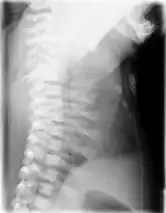

Lateral CXR of the same person above

This diagnosis is grouped with other chest problems called thoracic insufficiency syndrome (TIS). Diagnosis of Jeune syndrome can be made as early as before birth if signs and symptoms are apparent on an ultrasound; however, diagnosis after birth usually occurs through X-rays and genetic testing, such as the tests found on the Genetic Testing Registry Archived 2021-03-18 at the Wayback Machine (GTR).[9]